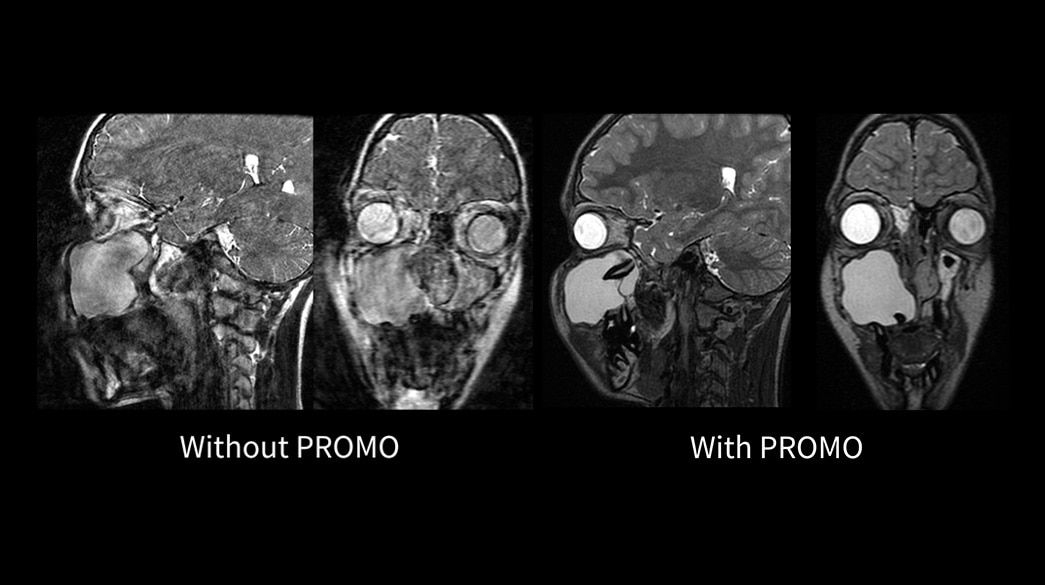

Consistent

Motion and distortion-reduced scans with high-resolution and contrast